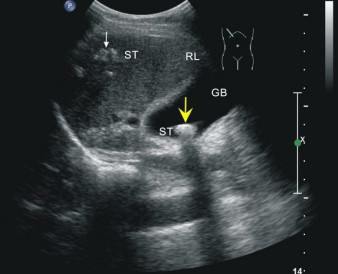

這位先生姓錢,自訴飲酒后出現(xiàn)胸骨后疼痛4小時(shí),呈壓榨性,持續(xù)不緩解,伴大汗、面色蒼白、惡心、欲吐,既往無(wú)高血壓、糖尿病、冠心病病史,吸煙史30年,偶有飲酒,入院時(shí)查體血壓為120/80mmHg,心率:98次/分,節(jié)律規(guī)整,未聞及明顯雜音。心電圖:竇性心律,心率98次/分,II、III、aVF導(dǎo)聯(lián)病理性Q波,ST段下移,不正常心電圖。不除外急性心肌梗死。急檢心肌酶及超敏肌鈣蛋白、淀粉酶,結(jié)果回報(bào)心肌酶、超敏肌鈣蛋白無(wú)明顯改變。疼痛時(shí)復(fù)查心電圖較前無(wú)變。胸痛癥狀仍持續(xù)不緩解,給予曲馬多止痛不改善。請(qǐng)示李桂武主任醫(yī)師,主任給予詳細(xì)詢問病史、癥狀及查體,患者膽囊區(qū)有壓痛無(wú)反跳痛,考慮患者可能存在膽囊性疾病,不排除腎結(jié)石,指示:急檢肝膽胰脾彩超及泌尿系彩超。我急忙陪著患者及家屬去門診彩超室做肝膽胰脾及泌尿系彩超。結(jié)果如下圖。提示膽囊結(jié)石。

請(qǐng)肝膽外科梁博主任會(huì)診后建議行CT檢查以進(jìn)一步明確診斷,肝膽胰脾CT結(jié)果可見膽囊不大,內(nèi)見高密度結(jié)節(jié),約10mm(IM33),膽總管無(wú)擴(kuò)張。建議轉(zhuǎn)入肝膽外科行手術(shù)治療。